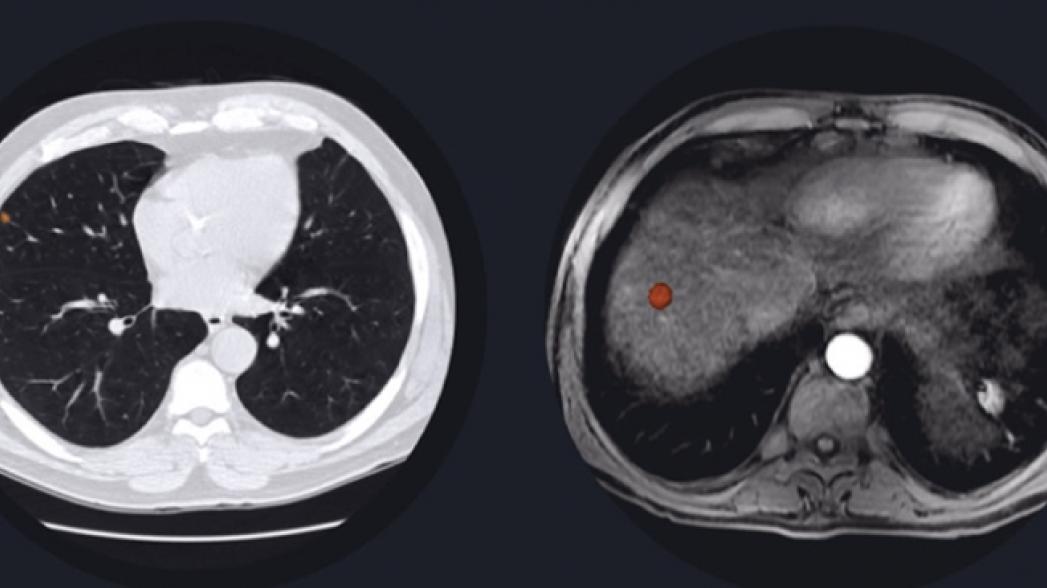

Американская компания Arteris получила разрешение от регулятора отрасли не клиническое использование своего пакета программ Arteris Oncology AI на базе технологий искусственного интеллекта. Это программное обеспечение предназначено для обнаружения раковых очагов на изображениях, полученных при компьютерной томографии легких (Lung AI) и сканах компьютерной и магнитно-резонансной томографии печени (Liver AI). Система использует методы искусственного интеллекта для выделения поражений и конкреций, и их оценки. Как показало тестирование, Arteris Oncology AI работает также качественно как сертифицированные радиологи.

Этот программный пакет, доступный через стандартный браузер, позволяет радиологам измерять и отслеживать развитие опухоли и подозрительных мест в органах человека. Поскольку система не требует использования какой-либо инфраструктуры, она относительно легко настраивается и используется, причем без необходимости как-то ее регулировать в будущем. Отметим, что это программное обеспечение соответствует всем условиям законодательного акта HIPAA* и аналогичных законов в 26 странах, включая Европу.